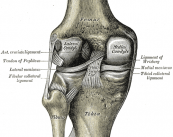

¿Qué son los meniscos? Conoce todo sobre Lesiones Meniscales

Los meniscos se encuentran en las rodillas y tienen funciones específicas. Existen varios tipos de lesiones y dependiendo de sus características, así como de la edad del paciente, el especialista determinará cuál es la mejor forma de tratamiento, la cual suele ser mediante cirugía. El tiempo de recuperación dependerá de cada caso.